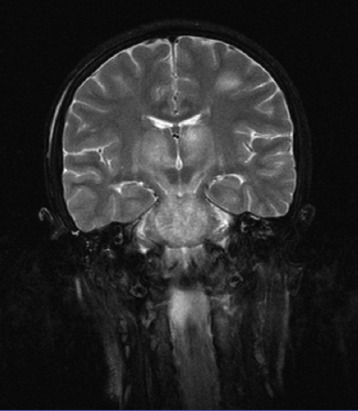

With a diagnosis of AHLE, our patient was treated with methylprednisolone (20 mg/kg pulse therapy), intravenous immunoglobulin (IVIG), acyclovir (30 mg/kg/d), and plasmapheresis (3-hour sessions for 3 times). After 29 days’ stay in the pediatric intensive care unit and under supervision of pediatric toxicologists and neurologists, she was extubated and attained a remarkable healing. Her MRI demonstrated improvement (figure 3). At one year’s follow-up, the treatment was completely successful and neurological examinations, comprised of mental status, motor skills, sensory skills, balance and coordination, reflexes, and functioning of the nerves, were all normal.

Figure 3.

The MRI demonstrated improvement after healing.